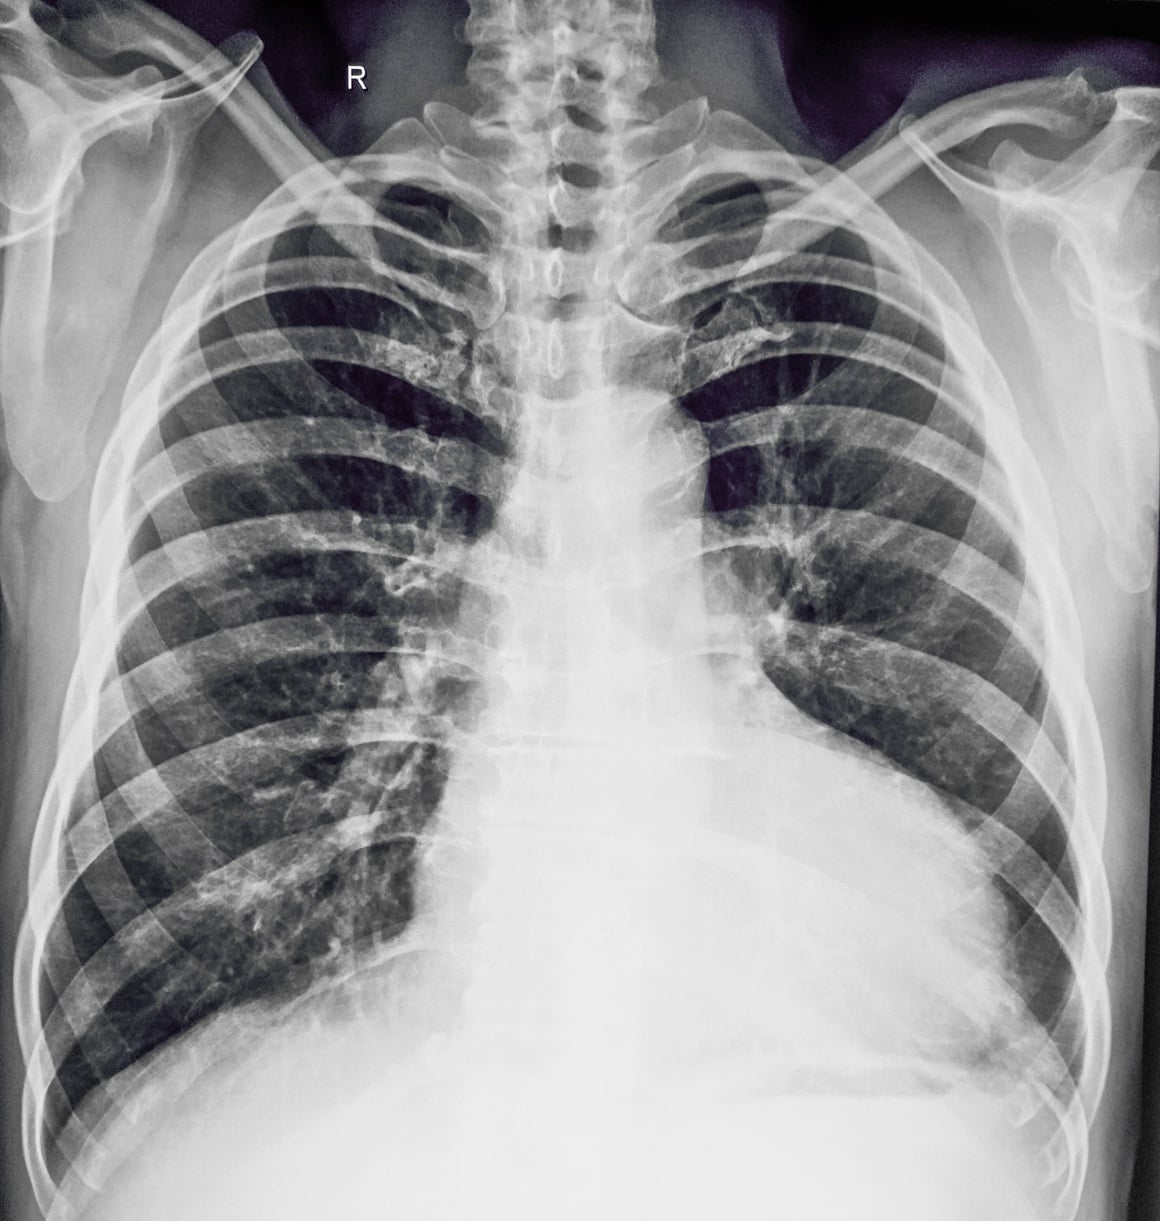

Dijagnostika kardiomegalije

Za dijagnozu se najčešće koristi ehokardiografija (ultrazvuk srca), koja pokazuje veličinu i funkciju srca. Dodatne metode uključuju: